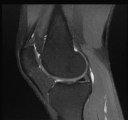

IRM du genou : définition, comment se passe un examen, et y a-t-il des risques ?

genou irm